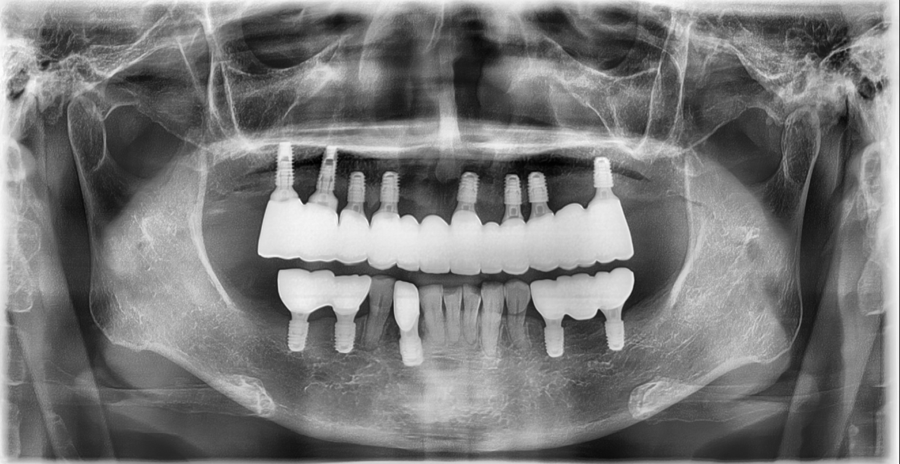

실제 수면임플란트 후 사진입니다. “임플란트 수술이 너무 무서워서 계속 미루고 있어요.” “치과만 가려고 하면 괜히 긴장부터 돼요.” 안녕하세요, 서울오브치과병원입니다. 임플란트가 필요하지만 수술이 무섭고 시간 내기 어려워서 계속 미루고 계신 분들이 많습니다. 이런 경우 잠실 수면임플란트는 충분히 고려해볼 수 있는 치...

실제 수면임플란트 후 사진입니다.